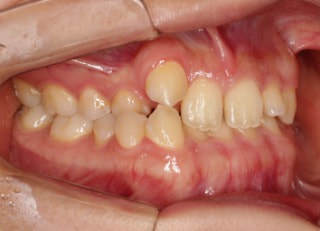

上顎2番矮小歯右下2番先天欠如

解説:下顎前突上顎劣勢長傾向で、上顎両側2番が矮小歯、右下2番先天欠如症例なので、上下前歯の幅径の比率を調節する必要があるケースです。(ご本人のご都合で治療中に来院できない期間がありました)

治療前